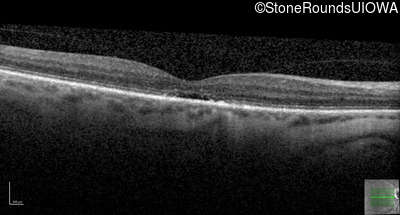

Age at visit: 55 years

The clinical features supporting the diagnosis of blue cone monochromacy in this patient include: stable reduced acuity, photophobia and very poor color vision since early childhood, a normal fundus appearance, normally sighted parents and three similarly affected male relatives on the maternal side of his family.